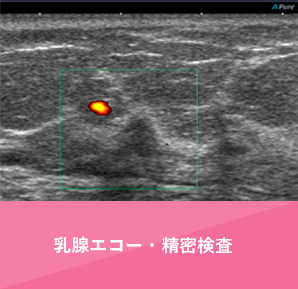

- 乳房に超音波をあてて、はね返ってくる音波を画像化した検査です。

“エコー”、”超音波”と呼ばれ、検査は同じです。

超音波を用いた検査で被曝がないため、妊娠中でも受診可能です。

外来で実施する乳腺エコー検査は、ターゲットとなる病変について、十分な時間をかけて検査を行います。 - ≫検査の詳細

乳腺外科外来で実施する乳腺エコー検査